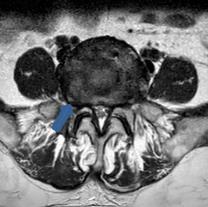

• 脊柱内镜侧后路联合减压术治疗腰神经根双卡综合征的临床疗效观察

2025, 31(12):25-32. DOI: 10.12235/E20250012

摘要 (122) HTML (46) PDF 10.14 M (90) 评论 (0) 收藏

摘要:目的 观察脊柱内镜侧后路联合减压术治疗腰神经根双卡综合征(DCS)的临床疗效、可行性、安全性和有效性。方法 回顾性分析2018年9月-2023年9月于该院就诊的50例腰椎退行性病变致腰神经根DCS患者的临床资料,根据手术方法不同,将患者分为观察组(37例)和对照组(13例)。观察组行脊柱内镜侧后路联合减压术治疗,对照组行非手术治疗。比较两组患者治疗前、治疗后1周、治疗后3个月、治疗后6个月和治疗后12个月的疼痛视觉模拟评分法(VAS)评分、Oswestry功能障碍指数(ODI)和日本骨科协会(JOA)评分。末次随访时,采用改良Macnab标准,评估临床疗效;采用腰椎MRI检查,评估椎间隙高度和椎间盘退变改良Pfirrmann分级。比较两组患者治疗的安全性(包括:并发症发生情况、复发情况和转手术治疗情况)。结果 50例患者均顺利完成治疗。两组患者术后VAS评分和ODI呈下降趋势,JOA评分呈升高趋势,观察组术后各时点VAS评分和ODI明显低于术前,且明显低于对照组,术后各时点JOA评分明显高于术前,且明显高于对照组,差异均有统计学意义(P < 0.05);观察组优良率为86.49%,明显高于对照组的76.92%,差异有统计学意义(P < 0.05);两组患者末次随访时,椎间隙高度和椎间盘退变Pfirrmann分级比较,差异均无统计学意义(P > 0.05)。两组患者围手术期均未出现神经损伤和脑脊液漏等严重并发症,观察组术后1例出现下肢放射性疼痛;观察组1例术后3个月出现腰椎间盘再突出;对照组有3例转手术治疗。结论 与非手术治疗相比,脊柱内镜侧后路联合减压术可更为安全、有效地缓解腰神经根DCS患者的疼痛,改善下肢功能,且早、中期临床疗效好。值得临床推广应用。